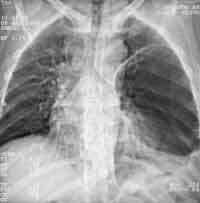

Чаще буллы выглядят как одиночные и множественные округлые полости, но встречаются и многокамерные буллы. Так же высока информативность метода РКТ при парамедиастинальных буллах (Рис. 2), которые практически не выявляются другими методами. Только с помощью компьютерной томографии можно идентифицировать каждую буллу, установить их количество, размеры и локализацию (Рис. 3).

Рис. 2. В правом реберно-позвоночном углу булла, не выявленная на обычной рентгенограмме.